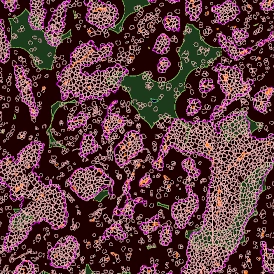

Despite the complexities of multiplexing for immunofluorescence image analysis, the ability to simultaneously record multiple channels has clear benefits in regards to the quality of information that can be obtained. The right tissue cytometer for image acquisition and data analysis can also make the process more straightforward.

TF SPECTRA is a multispectral imaging set-up capable of recording the emission of up to 8 markers when combined with our StrataQuest's unmixing algorithms. Many possible artifacts, like channel bleed-through, can potentially be corrected with the right post-processing software.

TF SPECTRA is designed, among others, for high-end immunofluorescence image analysis and uses tunable liquid crystal filters to offer much greater flexibility in the wavelength filtering than is achievable with standard filters. Such filters can be tuned at speed to build lambda stacks to rapidly help with data correction.